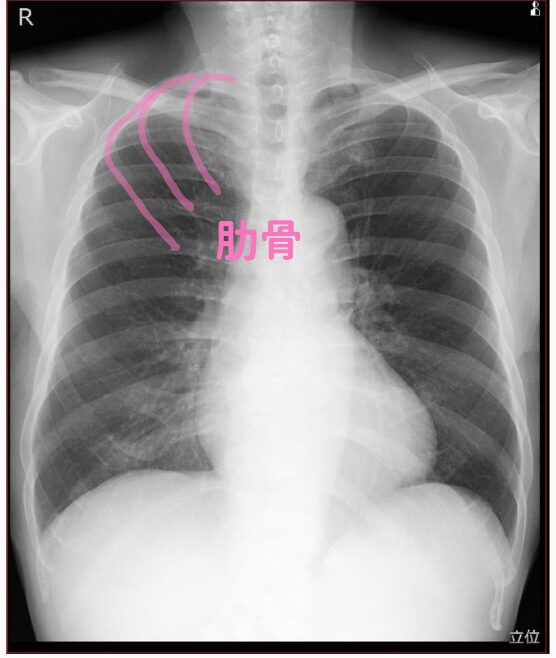

(3)肋骨

図では第1・2・3肋骨をピンクで描いています。

これは背中側の肋骨です。

前側の肋骨は肋軟骨が多いので心臓側はあんまり写りません。

胸水が溜まっている時、僕は肋骨も気にします。

心不全や肺がんはもちろんですが、肋骨骨折⇨血胸も考えます。